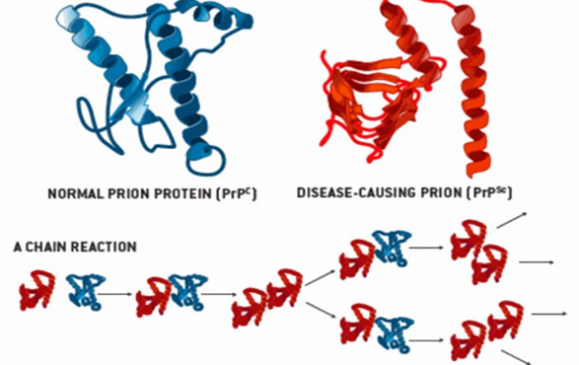

Biochemical defect- A prion is a protein type that can trigger normal proteins (PrPC) in the brain to fold abnormally. The normal function of this protein is unknown. The prion protein binds with a normal protein to alter its structure and, thus, functions. Misfolded proteins ((PrPSc) accumulate to form clumps in the brain, damaging the brain cells. The damaged brain gives a spongiform appearance under a microscope. Due to this characteristic, Prion disease is also called “Spongiform encephalopathy” (figure 3)

A)

Figure-3- A) Showing the transformation of a normal protein to a Prion protein (PrPSc) and B) Spongiform appearance of the brain in Prion disease.